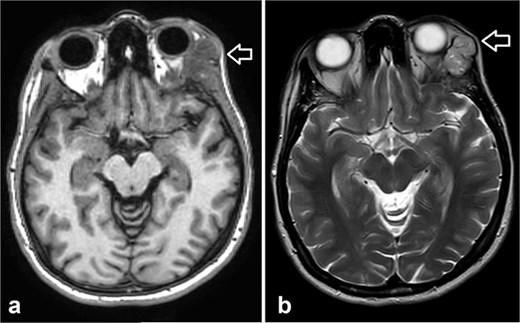

During follow-up, the patient complained of swelling at the left angle of the mandible and left lateral canthus. Orbit MRI showed local disease progression (Fig. 4). Ultrasonography of the left parotid region showed an irregular hypoechoic lesion in the left parotid gland. A PET scan revealed hypermetabolic malignant irregular soft tissue thickening within the lateral periorbital area of the left eye, consistent with a recurrence disease. Additionally, there is a new hypermetabolic irregular soft tissue mass in the left parotid gland with numerous bilateral scattered pulmonary nodules (Fig. 5). A biopsy from the left parotid gland confirmed the diagnosis of ACC, aligning with the primary tumor. The patient was diagnosed with lacrimal gland ACC with metastasis to the left parotid gland and the lungs. The Head and Neck multidisciplinary team proceeded with systemic chemotherapy using cisplatin and Navelbine. The patient started chemotherapy with good tolerance and clinical response and is now on regular follow-up with the oncology clinic.

Orbit MRI showed a lobulated, well-defined lesion, hyperintense to intermediate on T2W (b) and hypointense on T1W (a) structures with cystic changes, measuring 2.3 × 1.9 cm and 2.6 × 1.6 cm, compared with the previous study, the lesions have increased in size.

MRI is the preferred modality to detect bony invasion and perineural spread. ACC usually appears as T1 isointense and T2 hyperintense with enhancement . Our patient's orbit MRI showed a lobulated, well-defined lesion, hyperintense to intermediate on T2W and hypointense on T1W structures with cystic changes.